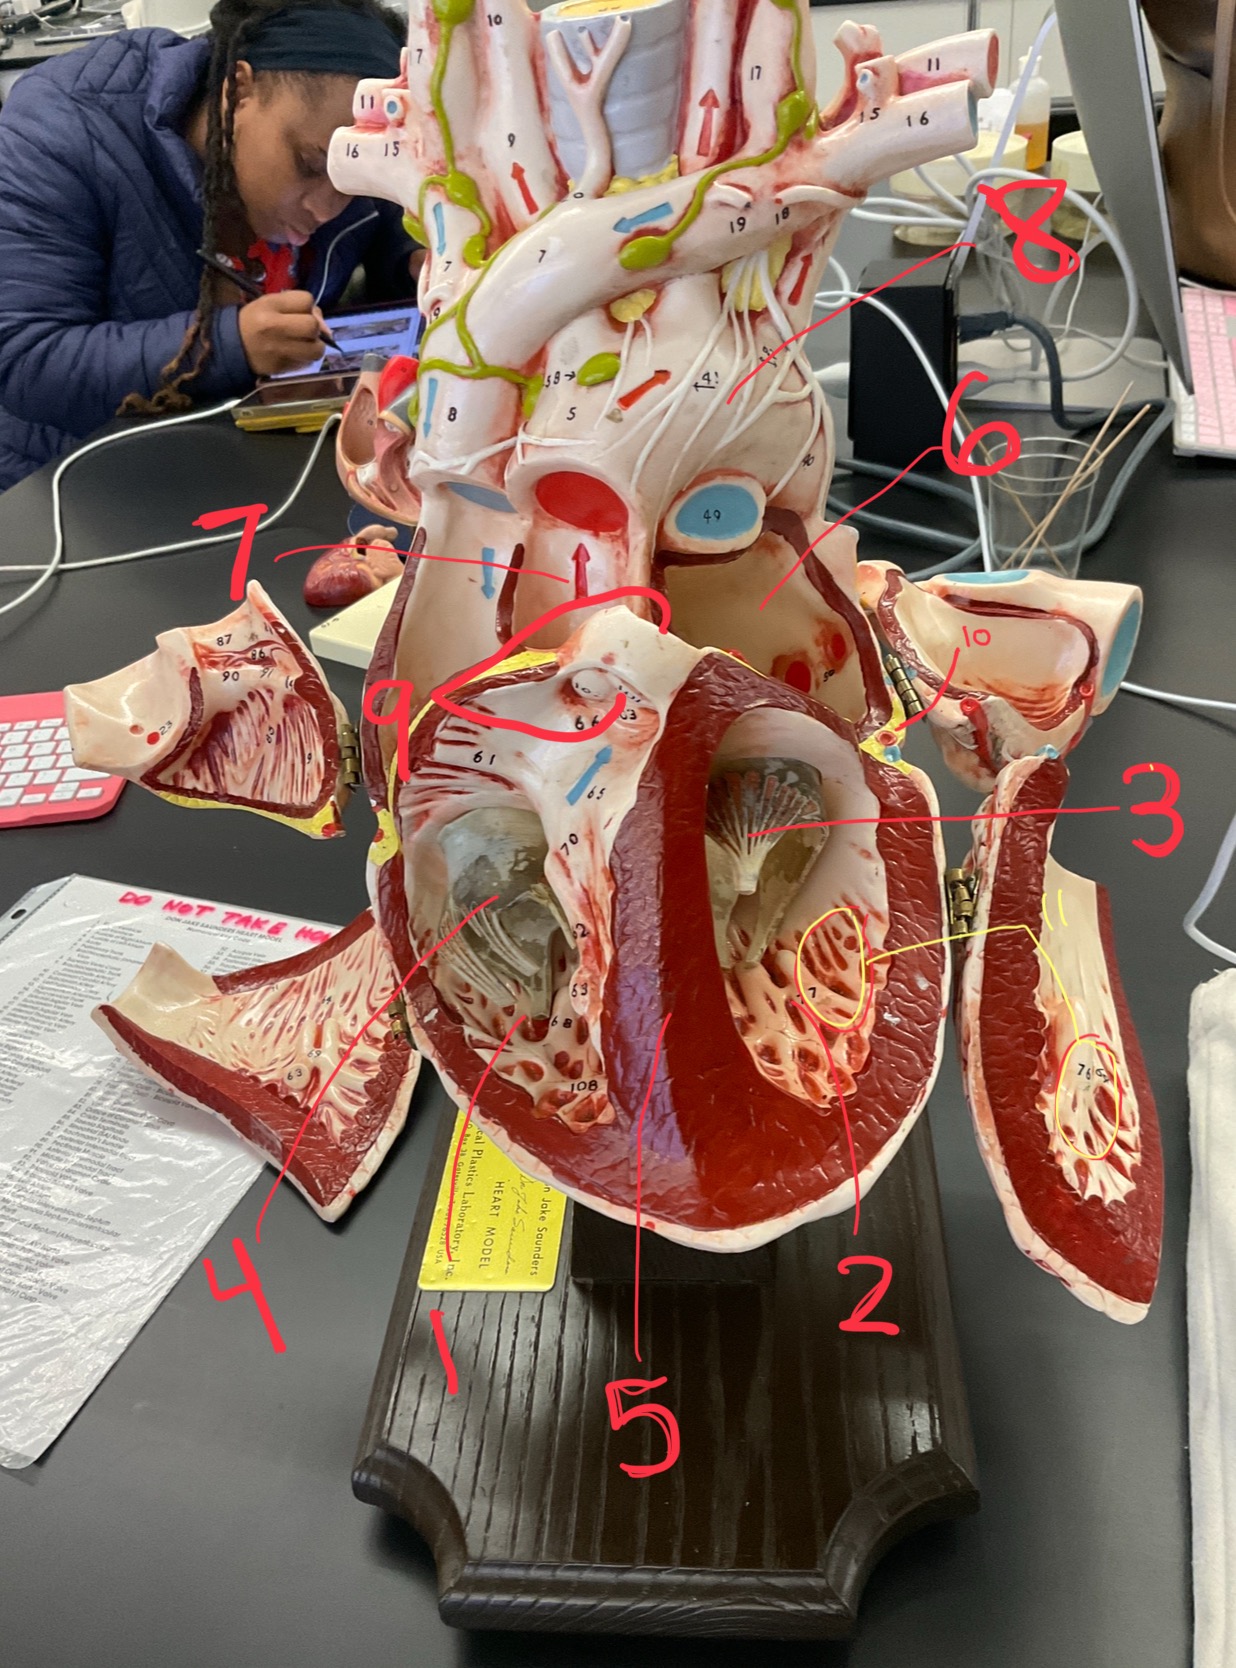

1

epicardium

2

3

endocardium

3

2

myocardium

4

1

coronary sinus

5

2

inferior vena cava

6

3

superior vena cava

7

1

right ventricle

8

2

left ventricle

9

3

bicuspid

10

4

tricuspid

11

5

interventricullar septum

12

6

left atrium

13

7

aorta

14

8

aortic trunk

15

9

pulmonary semi-lunar valve

16

10

atrevoventricullar sulus

17

11 (not smooth part)

trubeculae carneae

18

1

papillary muscle

19

2

chordae tendineae

20

4

pulmonary trunk

21

6

aortic trunk

22

aortic semi lunar valve

New cards

anterior inter ventricular sulcus